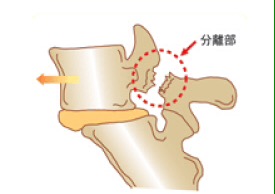

「腰椎分離症」と聞きなれない専門用語を用いてスミマセン…

腰の骨の骨折。

疲労骨折が起きている状態です。

腰椎分離症は、

体を反る動きで痛めやすいんですね。

体を反り、この突起の部分にストレスがかかる事で、ポキッと疲労骨折してしまうんです。